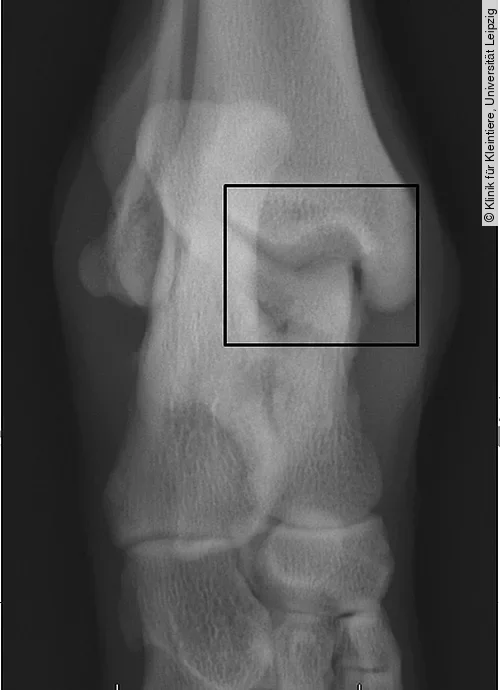

Projektionsradiografie Tarsokruralgelenk

Standardmäßig werden zur Projektion des Tarsalgelenks eine mediolaterale und eine dorsoplantare/plantodorsale Aufnahme angefertigt. Besteht der klinische Verdacht einer OCD und lassen sich auf den genannten Projektionen aber keine Hinweise dafür feststellen, werden dorsoplantare Aufnahmen mit Flexion des Tarsus angeraten (Skyline) [1], [22].

Häufig ist eine Abflachung des medialen Talusrollkamms im Sinne eines subchondralen Knochendefekts zu erkennen; seltener auch des lateralen Rollkamms. Im Bereich des Defekts ist im Falle einer Mineralisation eine isolierte Knorpelschuppe zu erkennen. Die schnell einsetzende, meist hochgradige Arthrose führt zusätzlich zu einer unruhigen proximalen Kontur (Abb. [ 9 ]). Ein weiterer Hinweis ist ein erweiterter medialer Gelenkspalt des Tarsokruralgelenks [1], [18], [22]. Mithilfe der Computertomografie können Ausmaß und Lokalisation der Defekte jedoch weitaus sicherer dargestellt werden [11].